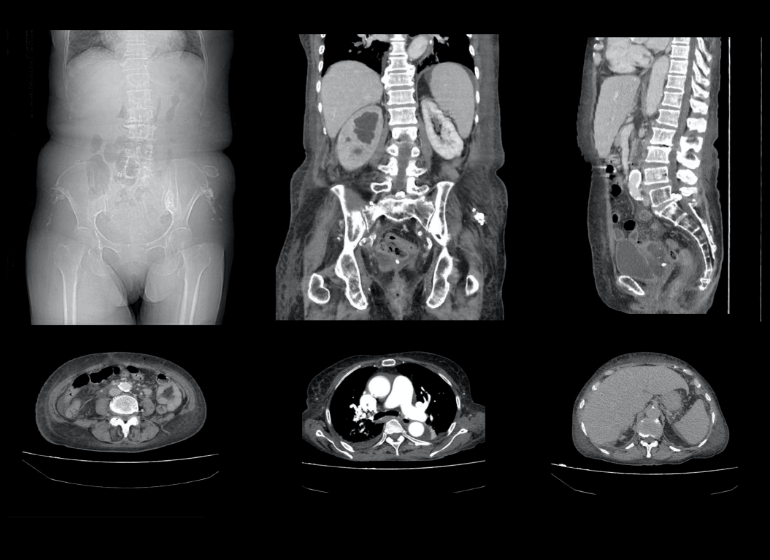

多くの場合、医師は症状や病歴に基づいて腎臓結石を診断できます。 CT スキャン(CAT スキャンとも呼ばれます) は、一連の X 線を使用して体内の画像を作成します。 CT スキャンでは、従来の X 線よりも詳細な画像が得られます。

場合によっては、CT スキャンが造影剤を使用して実行されることがあります。造影剤は口から摂取するか、静脈 (IV) ラインを通じて静脈内に投与します。医療従事者が臓器をより明確に見るのに役立ちます。通常、腎臓結石の診断には、造影剤を使用しない CT スキャンが実行されます。

各スキャンは、腎臓の上部から膀胱の底部までの領域をカバーできます。これらのスキャンにより、医師は結石の大きさを確認したり、腎臓から膀胱につながる尿管の異常を特定したりすることもできます。